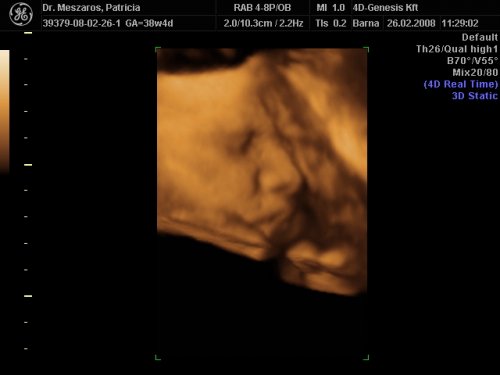

31 hetes